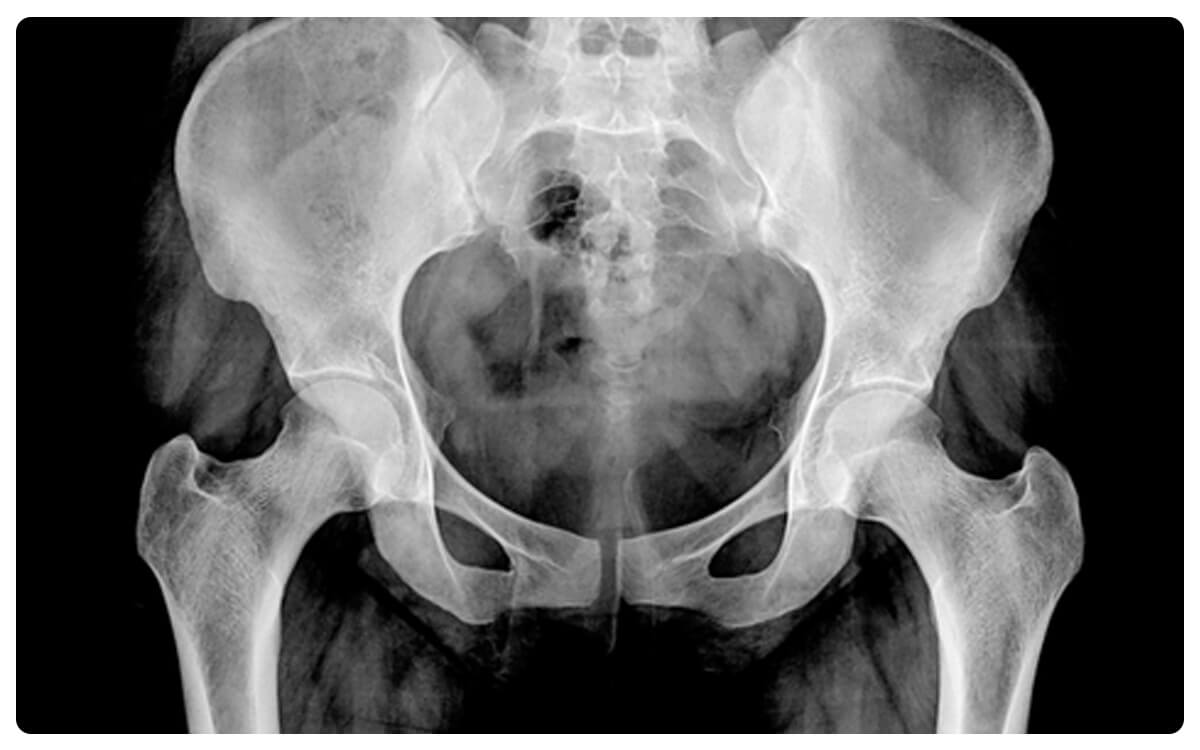

La Radiografía de Pelvis en Proyección Anteroposterior (AP) se posicióna como una herramienta clave en la radiología diagnóstica, ofreciendo una visión integral y detallada de la región pélvica. Mediante la emisión controlada de radiación, esta técnica no invasiva proporciona imágenes bidimensionales que permiten evaluar la estructura ósea y las articulaciones en la zona de la pelvis desde una perspectiva frontal.

La Radiografía de Pelvis en Proyección AP desempeña un papel fundamental en la detección y diagnóstico de condiciones como fracturas, malformaciones y otras patologías óseas y articulares, proporcionando información esencial para la toma de decisiones clínicas informadas y el manejo adecuado de las afecciones relacionadas con la pelvis.